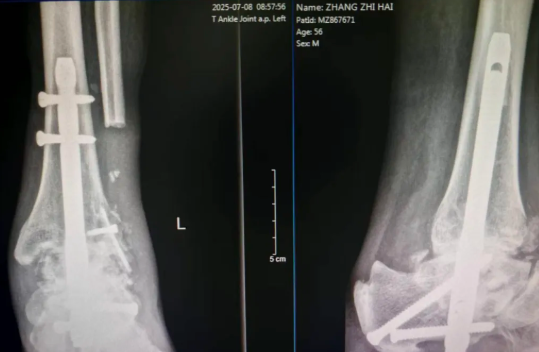

术前X线影像学检查提示:距骨存在塌陷性坏死;踝关节间隙弥漫性狭窄,关节边缘骨质增生伴关节面毛糙;且距下关节间隙变窄、伴关节面硬化及周围骨质增生,提示距骨坏死已引发多关节(踝关节、距下关节)受累的退行性关节炎改变,关节结构破坏及功能受损明显,为终末期创伤性踝关节炎伴距骨坏死。

术后2月复查X片显示关节已有融合迹象